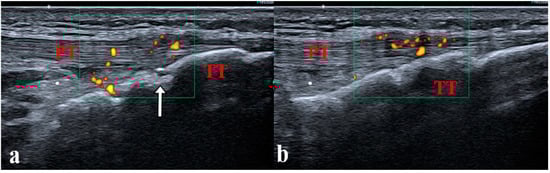

- Laurell, L.; Court-Payen, M.; Nielsen, S.; Zak, M.; Boesen, M.; Fasth, A. Ultrasonography and Color Doppler in Juvenile Idiopathic Arthritis: Diagnosis and Follow-up of Ultrasound-Guided Steroid Injection in the Ankle Region. A Descriptive Interventional Study. Pediatr. Rheumatol. Online J. 2011, 9, 4. [Google Scholar] [CrossRef] [PubMed]